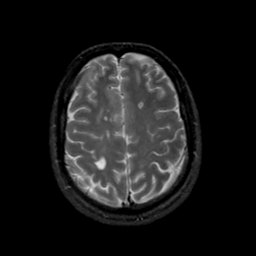

MR Study #17, July 7, 1991 -- Slice #38

[Home][Help][Clinical][Tour 1][Tour 2] Slice 38